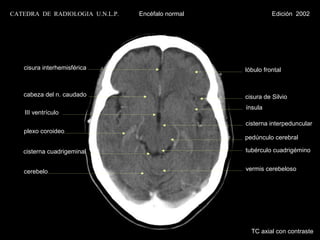

cisura interhemisférica

lóbulo frontal

cisura de Silvio

ínsula

hipotálamo

plexo coroideo                                 cisterna interpeduncular

pedúnculo cerebral

asta temporal

IV ventrículo                                  tubérculo cuadrigémino

cerebelo                                       vermis cerebeloso

lóbulo occipital

TC axial con contraste